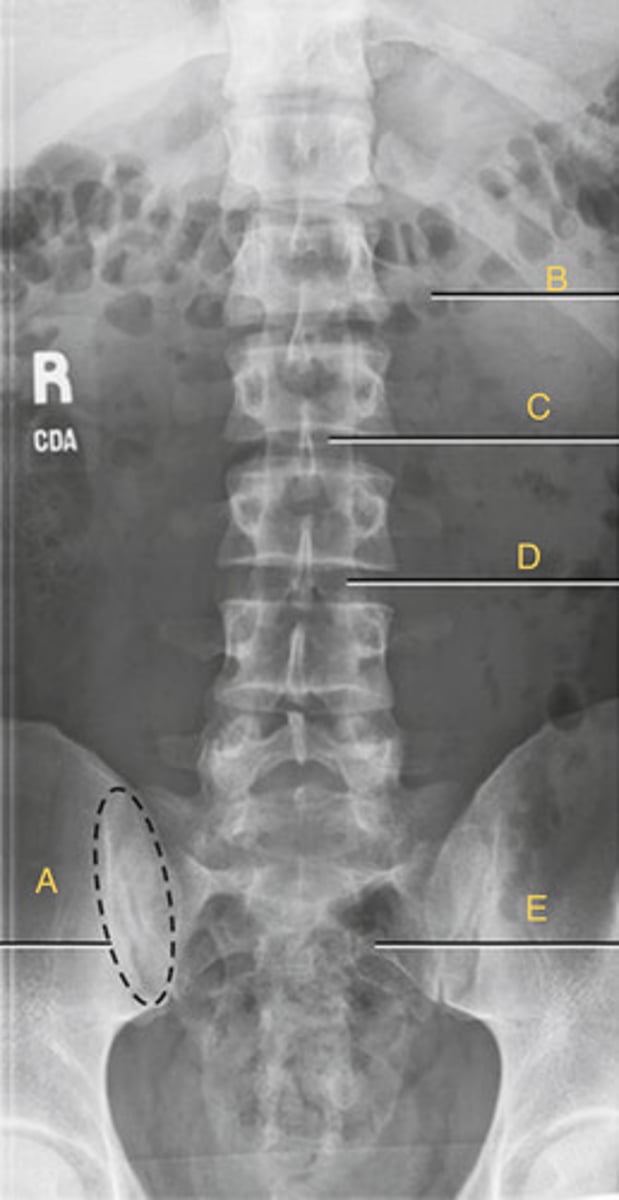

L2 Pedicle

A.

L2-3 intervertebral foramina

B.

L3-4 intervertebral joint space

C.

L4 body

D.

L5-S1 articular process

E.

Sacrum

F.

Greater sciatic notch

G.

L5-S1 joint

H.

Lateral Lumbar

What position?